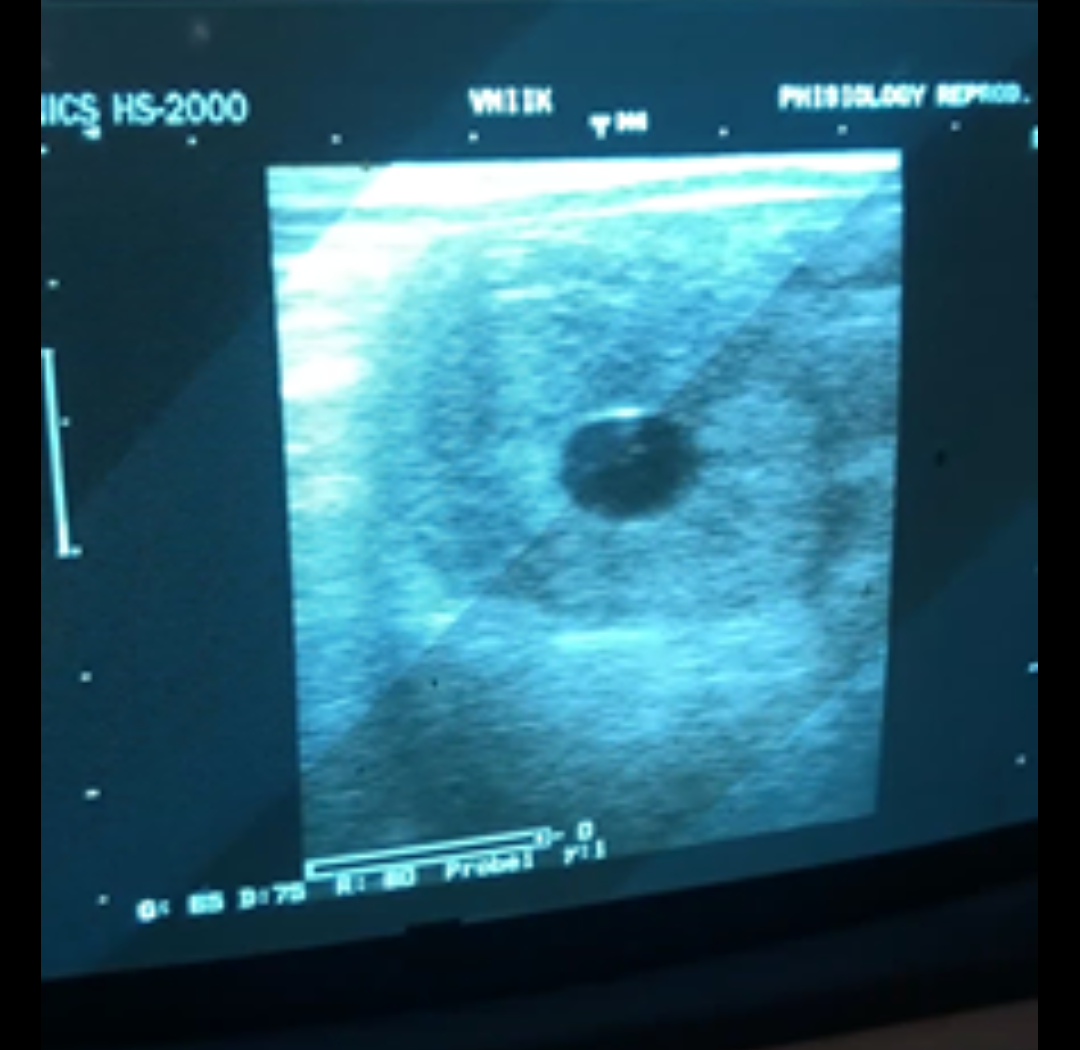

Ладно, это не мои проблемы, жеребец наморожен и в тот же день кобылу осеменили. Через 11 дней выяснили, что развился эндометрит. Кобыла осталась в чужой конюшне на неизвестный срок, началось лечение. В процессе лечения выявили редкую проблему - попадание мочи во влагалище (уровагина), соответственно моча может попадать в матку при открытой шейке. Что видимо и произошло при осеменении. Успешность зажеребления такой кобылы сильно снижается и не понятно как это лечить. И самое плохое - заранее известно, что дорогостоящие дозы будут слиты в унитаз с большой вероятностью. Но мы с кобылой попали в руки замечательному профессионалу - Елене Солодовой. Она успешно пролечила эндометрит, мыла кобылу до осеменения, после и ещё через 12 часов.

Результат

Screenshot_20200722-071912.png

Вот теперь и думай - ведь все складывалось не просто так, и все отказы и технические сложности нам дались неспроста, и сложилось в результате так как и должно сложиться ?‍♀️ не попади мы к Елене Солодовой и время бы потеряли, и неизвестно смогли ли выявить такую проблему.